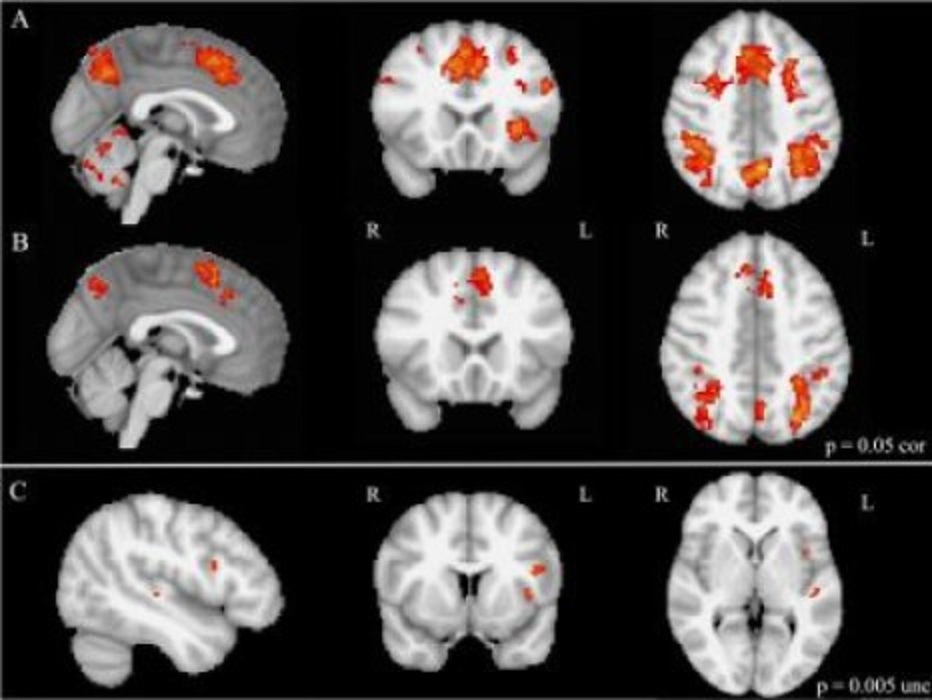

Imágenes de resonancia magnética funcional durante el cambio de tarea mental: Las filas A y B muestran la activación del cerebro en niños musicalmente entrenados y no entrenados, respectivamente. La fila C muestra las áreas del cerebro más activas en niños musicalmente capacitados que en niños no entrenados musicalmente. Fuente: Laboratories of Cognitive Neuroscience del Hospital Infantil de Boston.

En el análisis con fMRI, los niños con formación musical mostraron además una mayor activación de áreas específicas de la corteza prefrontal, en el transcurso de una prueba que les hizo variar entre diversas tareas mentales. Las áreas cerebrales sobreactivadas fueron el área motora suplementaria (encargada de la planificación y coordinación de movimientos complejos), la zona presuplementaria y la corteza prefrontal ventrolateral. Se sabe que estas regiones están relacionadas con la función ejecutiva.